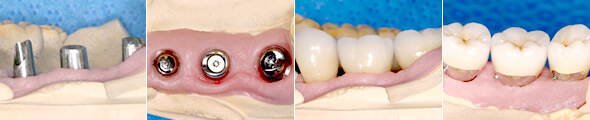

模型シミュレーション

step.1

まずは、歯の型をとる工程を行っていきます。

step.2

インプラント

精巧に作成した歯ぐきの模型です。他の医院ではあまり作成されないこだわりの方法です。インプラント直後の歯ぐきと、しばらくたって落ち着いた歯ぐきは、かなり違う形態になっています。

歯ぐきを模型化シミュレーションすることで、天然歯に近いインプラント治療ができるのです。

step.3

そして、歯が完成致しました。

実際の治療

治療①

期間 約3ヶ月 7回

内容 欠損部にインプラントを4本埋入し固定式セラミッククラウンを装着

※このケースはブリッジが無理で義歯(部分入れ歯)かインプラントが適応

メリット ・残存歯にかかる負担を軽減

・奥歯でしっかり噛むことができる

デメリット ・入れ歯に比べ費用がかかる